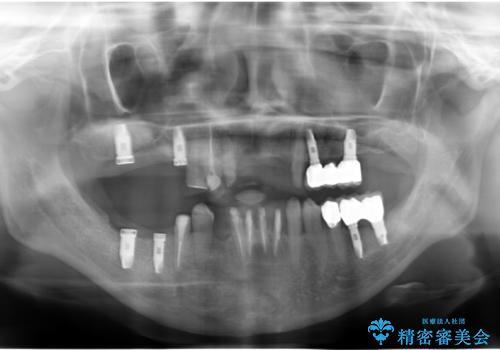

歯周病 全顎治療

- 前歯の見た目、入れ歯による噛めないことの改善を求めて来院されました。

検査により全顎的な歯周病治療、欠損のインプラント補綴、根管治療が必要な状態であることをお伝えし、治療を計画します。